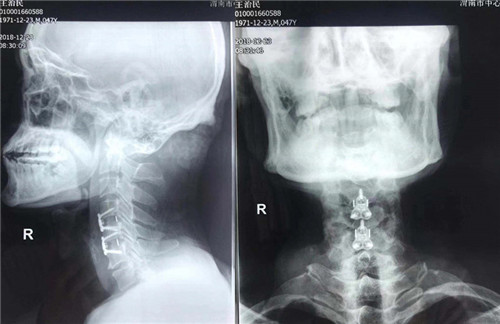

术前

因该患者病情较急,症状明显,骨一科主任翁润民、副主任医师程福宏,杨杰及主治医师张楠经讨论决定于当天下午急诊为其进行手术。由程福宏副主任医师主持手术。因术前诊断明确并抓住了最佳治疗时间,患者肢体症状恢复较好,功能改善明显,现患者自觉肢体麻木症状消失,上下肢肌力恢复并逐渐增强,各项指标也慢慢恢复正常。患者及家属都非常满意。